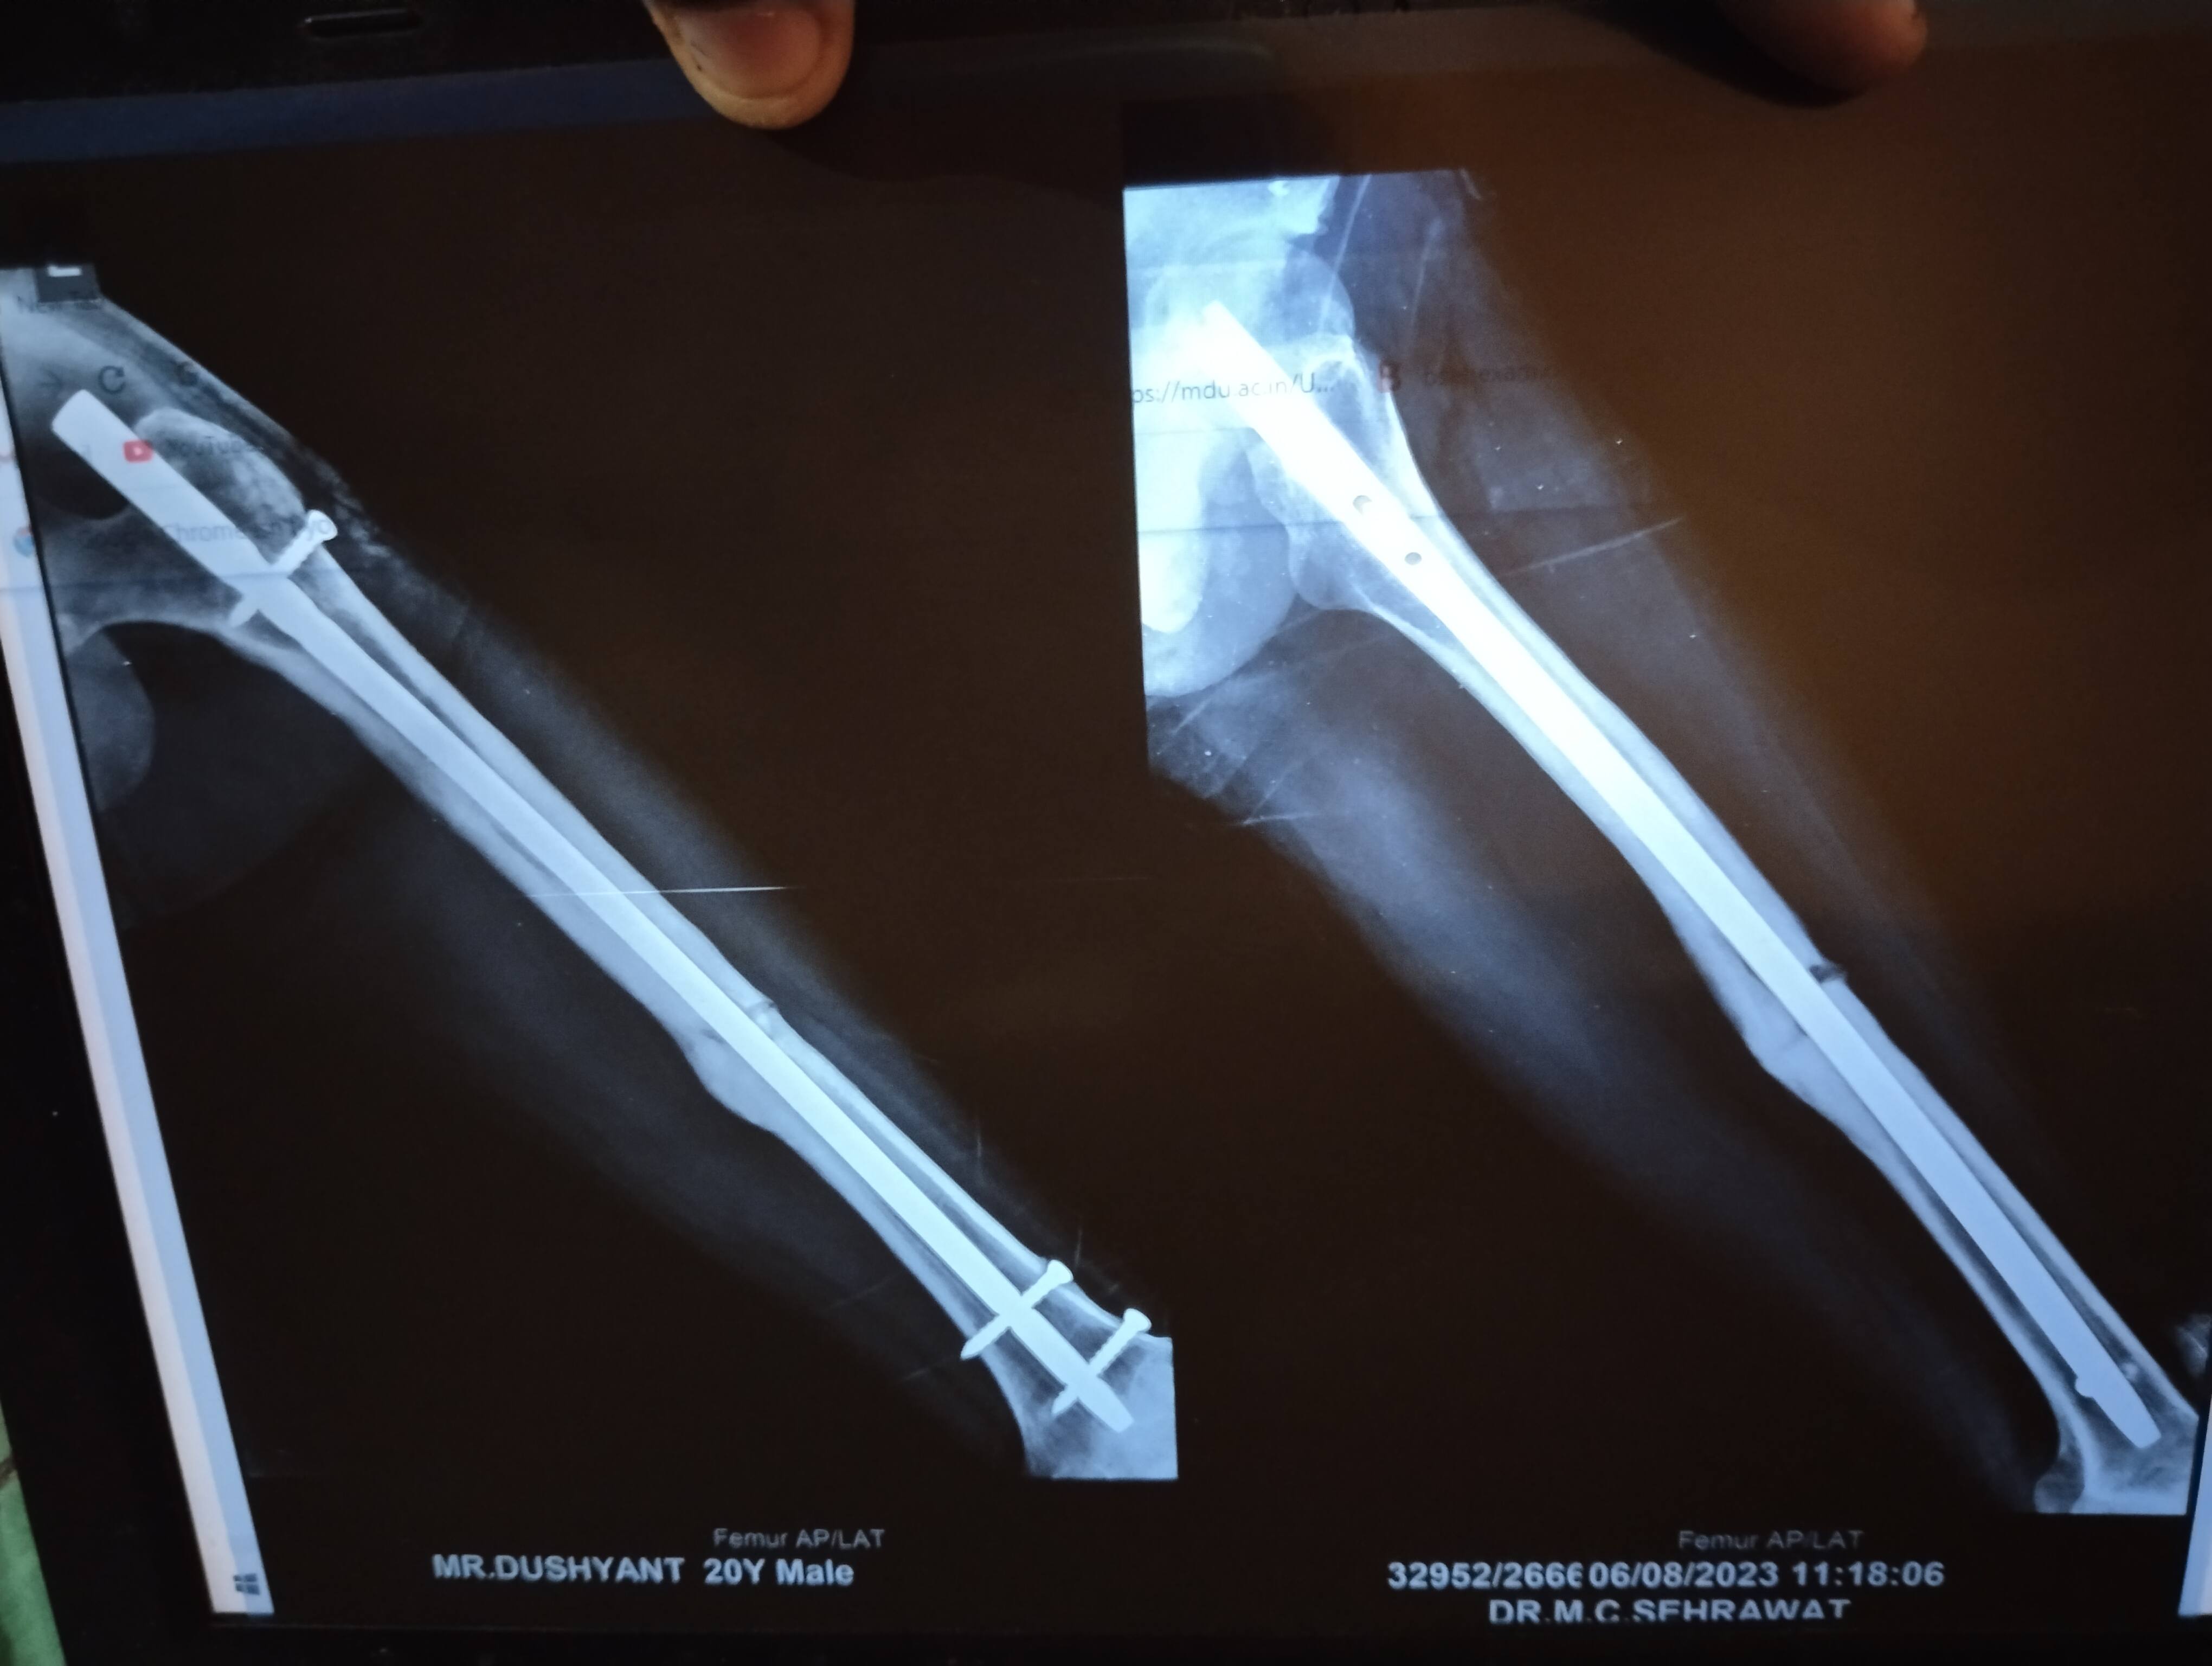

This is my femoral shaft fracture which happened ast year on 8 august 2022 Now its been 1 year Should i remove the implant or not Is there any complication after removal.of implant